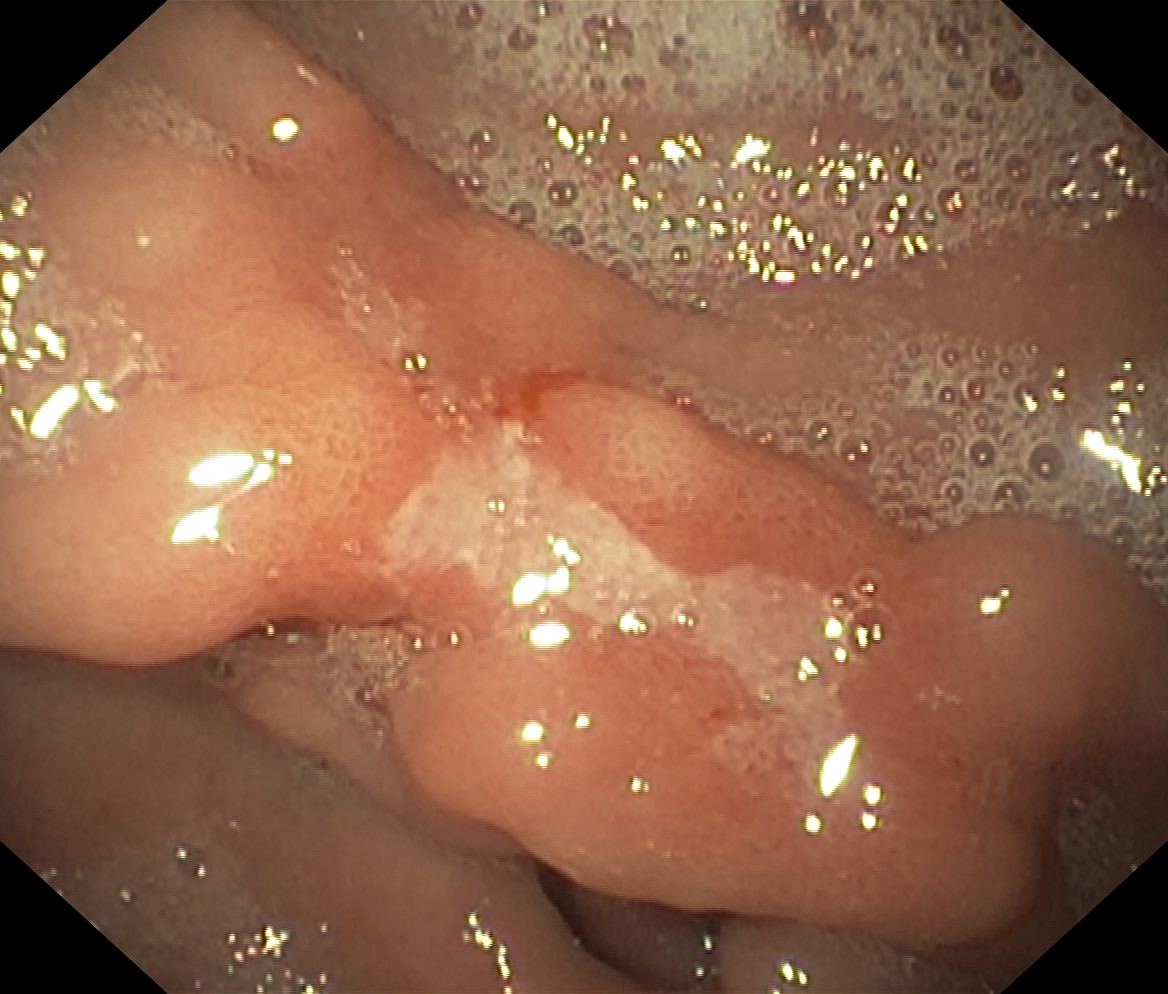

Wrzód trawienny